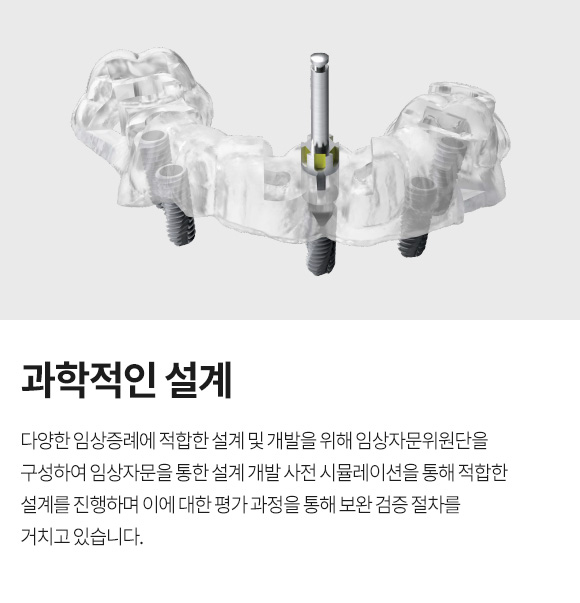

Osstem Implant 핵심